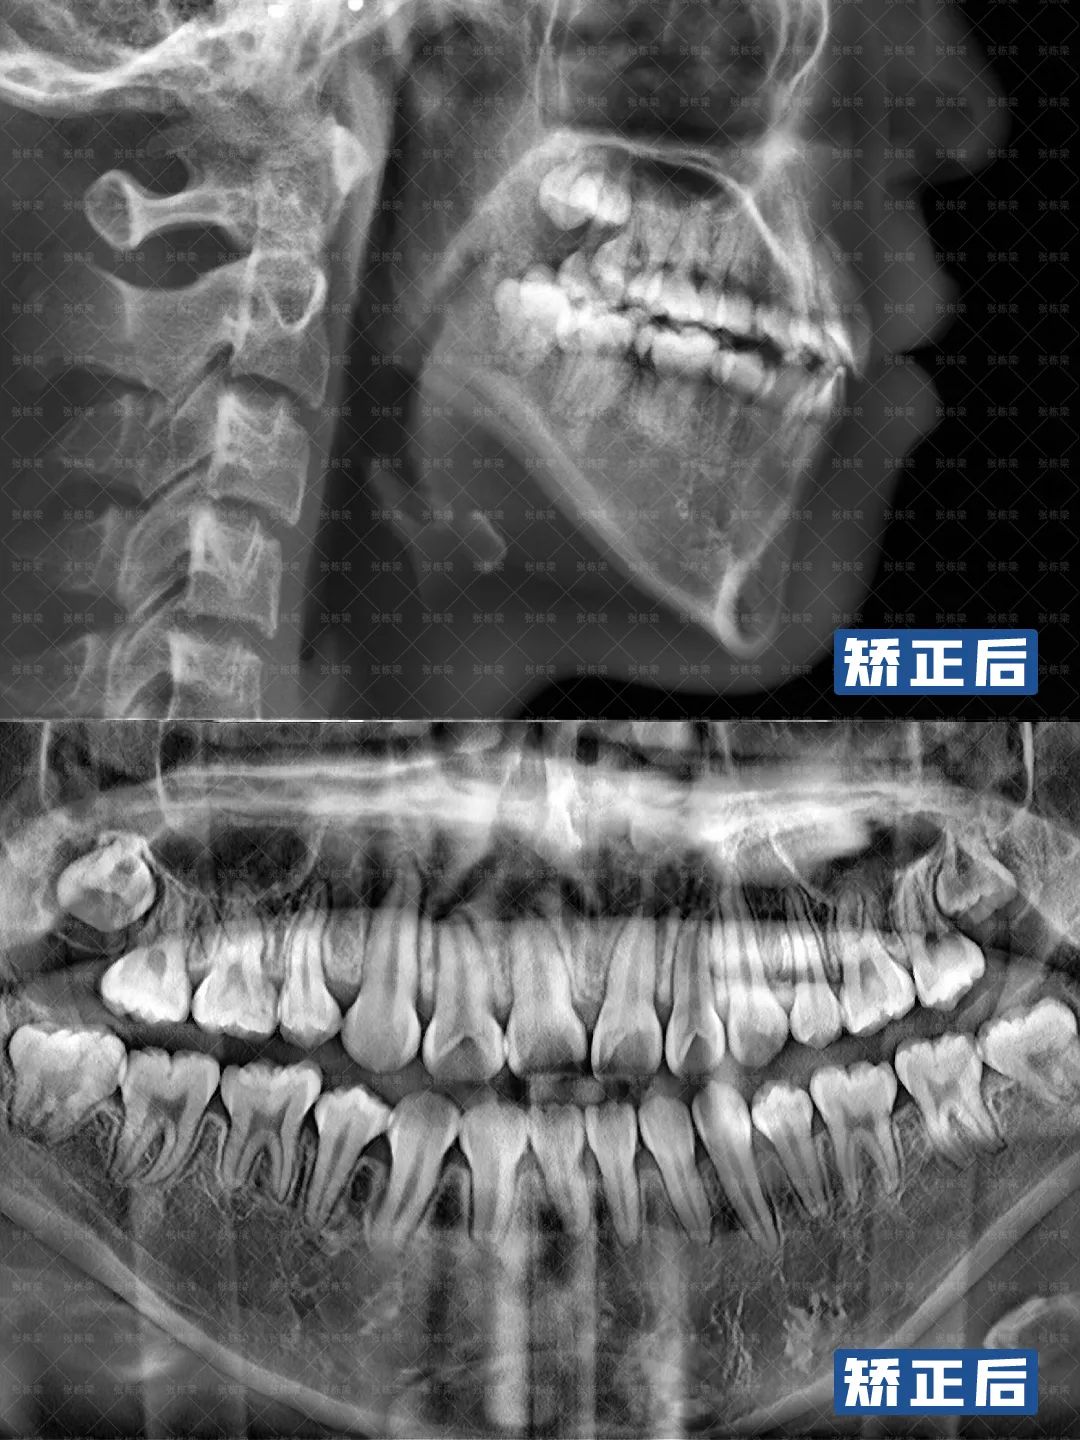

适当压低下后牙,整平下颌颌平面,解除前牙开颌,建立前牙正常覆合覆盖;

因为是凸面型,双侧磨牙近中关系,牙齿矫正需要通过丢失转矩内收上下颌,改善开颌,调整牙齿咬合,达到正常覆合覆盖。

牙齿矫正结束后,从牙齿上看,开颌解除,上下前牙牙转矩角度正常,前后牙距离关系恢复正常,尖窝关系良好,上下牙弓也恢复协调。

从面型上看,下巴前伸,颏肌放松了,面部肌肉轮廓更加协调、放松,上牙排列与笑线弧吻合,笑容饱满。